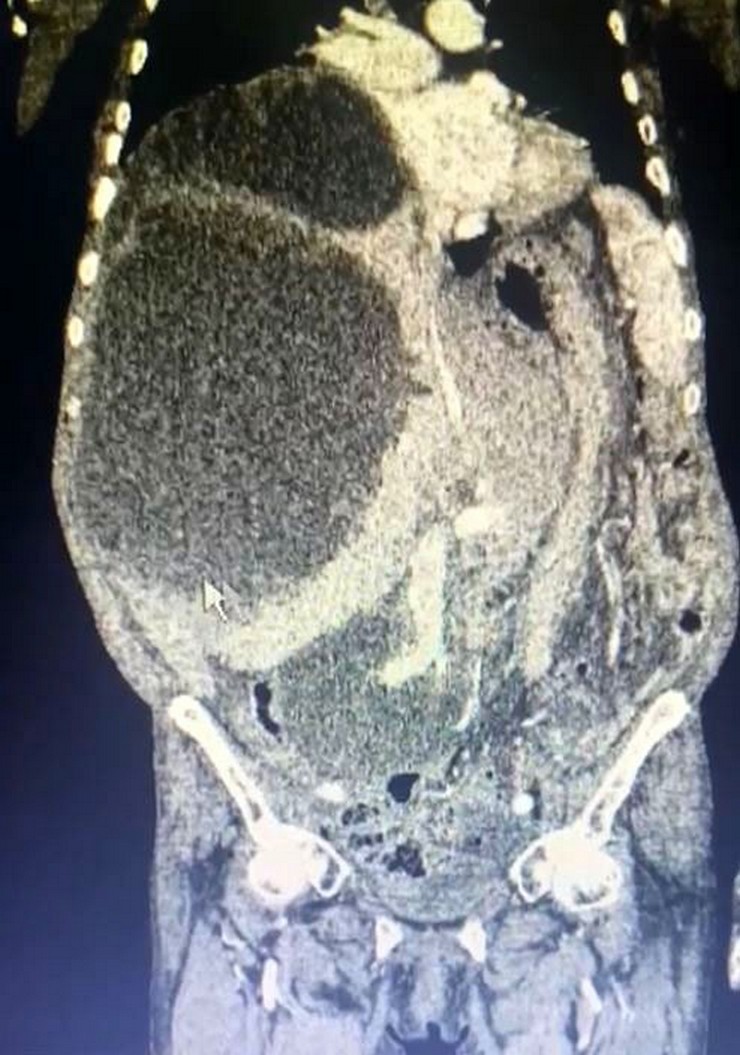

Çiftçilik yapan Asiye Taşdelen karnındaki şişlik ve ağrı nedeniyle Trabzon Kanuni Eğitim ve Araştırma Hastanesi’ne başvurdu. Taşdelen’e sağlık görevlileri tarafından yapılan muayene ve görüntüleme tetkiklerinde karaciğerinde 90 santimetreye ulaşarak karnını kaplayan 3 ayrı kedi-köpek kisti saptandı. Hasta için ameliyat kararının verilmesiyle 2 saat süren operasyon sonucunda Genel Cerrahi Uzmanı Operatör Dr. İsmet Çelik ve Gastroenteroloji Uzmanı Doç. Dr. Aydın Aktaş tarafından kistlerin 2’si çıkarılırken 1’inin içi boşaltılarak kontrol altına alındı. Dünya literatüründe 90 santimetreye ulaşarak tüm karnı dolduran bir kist ile ilk kez karşılaşıldığını ifade eden Dr. Çelik, kedi-köpek kisti olarak bilinen hastalığın bulaşma yollarını anlattı. Dr. Çelik, genellikle sokak hayvanları ile veteriner kontrolü yapılmayan evcil hayvanların dışkısıyla doğrudan temas veya dışkı bulaşan toprak, su veya yiyecekler yoluyla insan vücuduna geçen parazitlerin bu hastalığa neden olduğunu ifade etti. Dr. Çelik, kistin zamanla karaciğer, akciğer ve diğer organlara yerleşerek ciddi sağlık sorunlarına yol açabileceği konusunda uyarılarda bulundu.

Hastanın tüm karnının kistle kaplı olduğunu ifade eden Dr. Çelik, “Trabzon’da Kanuni Eğitim ve Araştırma Hastanesi bir ilke vesile oldu. Hastamız Gümüşhane’den karın şişliği ve ağrısı ile bizlere müracaat etti. Geldiğinde ileri tetkikleri yaparak, tüm karnını dolduran bir kitle ile karşılaştık. Durumu detaylandırınca kistin oluşumunu kedi ve köpekten kaynaklı olduğunu gördük. Hastamızın yandaş hastalıkları vardı. O hastalıkları ekarte edebilmek için ilgili branşlarla birlikte vakayı değerlendirdik. Hastamızın ameliyat olabilirliğini tartıştık. Konsey kararı ile ameliyatına karar verdik. Hastamızın karaciğerinde 3 ayrı kist vardı. Tüm karnı kist ile kaplıydı. 2 tanesinin tamamına çıkardık. Diğerini ise kontrole alarak içini boşalttık. Dünya literatüründe 90 santimetreye ulaşarak tüm karnı dolduran kist görmedik. Ameliyatımız 2 saat sürdü. Hastamızın safra yolları kontrol edildi. Hastamızın durumu gayet iyi. Solunum cihazından bağımsız olarak kendi başına solunum yapabiliyor. Yarın da servise alacağız” dedi.